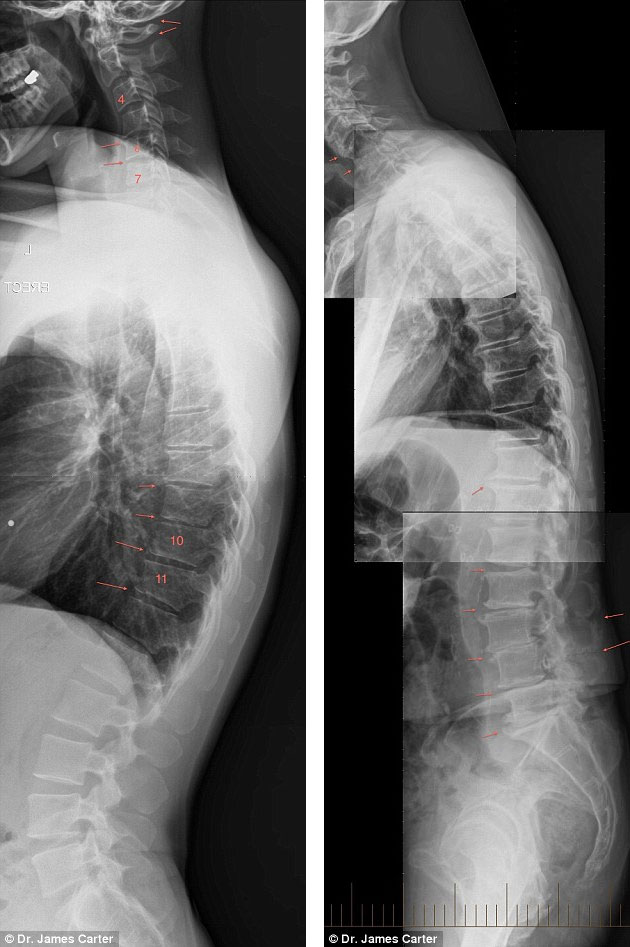

Az SMS-nyak és a tablet-hát kifejezéseket először James Carter ausztrál orvos vezette be, amikor olyan röntgen-felvételeket tett közzé, melyen nagyon fiatal, akár 6-7 éves gyerekek nyaka és háta látható, a rajtuk fellelhető jelentős elváltozásokkal. A szakember, aki korábban az Australian Spinal Research Foundation (Ausztrál Gerinckutató Társaság) elnöke volt, a jelenség széles közben való terjedésére hívja fel a figyelmet számos más ortopéd orvos kollegájával egyetemben.

A helyzet napjainkra odáig fajult, hogy a legfrissebb generációk tagjai már a szüleiknél is többet ülnek és náluk is több digitális eszközzel rendelkeznek, ami azt is jelenti, hogy még többet van egészségtelen pozícióban a gerincük és a nyakuk. Ez őket ráadásul hatványozottan érinti, hiszen növekedésben vannak.

A kifacsart testhelyzetek, elsősorban az előre biccentett nyak és a lefelé, a telefont bámuló fejtartás nem csak ülés vagy fekvés, de közlekedés, álló testhelyzet közben is jelentkeznek. Ezek nem csak maradandó nyaki problémákat okoznak, de kihatnak a teljes gerincszakaszra és hozzájárulhatnak akár a púposság kialakulásához is.